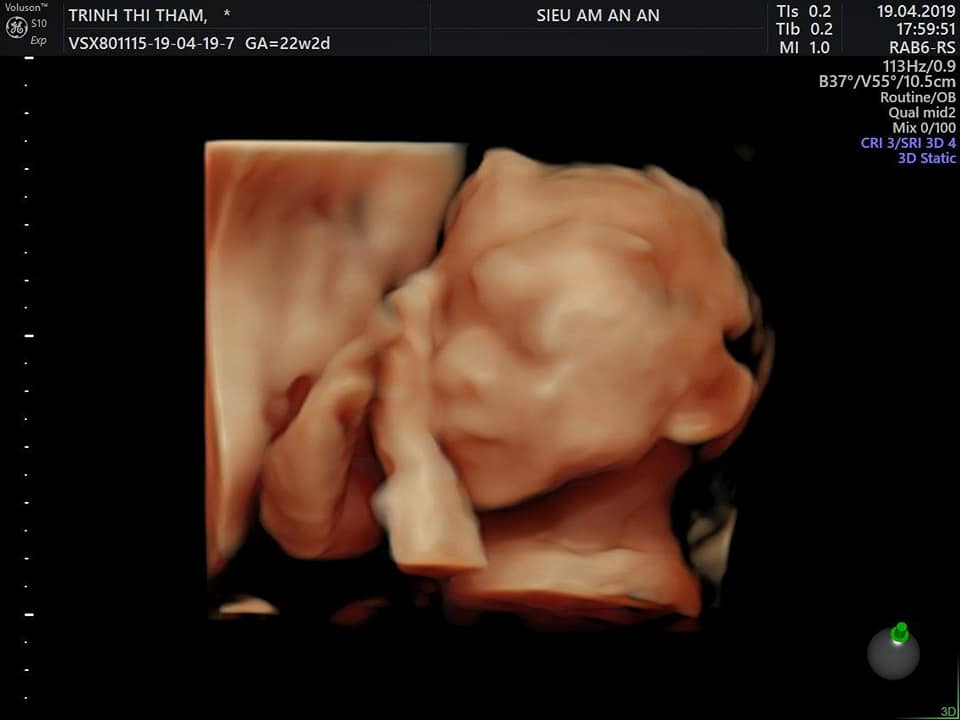

Mình mang bầu tập 1 bị sảy ở tuần thứ 6. Sau đó 3 tháng mình có bầu lại. Mình theo dõi khám ở PK An An. 3 tháng đầu mình phải sử dụng thuốc nội tiết để giúp thai phát triển tốt. Dks của mình là 21/8 ( theo kinh 3 tháng đầu). Nghề nghiệp của mình là điều dưỡng nên cứ hàng tuần nào mình cũng siêu âm tại cơ quan. Và các mốc quan trọng thì kiểm tra tại An An. 26w mình bị tiểu đường thai phải nhập viện bạch mai điều trị theo dõi 3 ngày. Sau ra viện thì chỉ điều chỉnh ăn uống và kiểm tra test đường tại nhà. 28w mình có cơn gò nhiều. Bs Nam _ S/â An An kê cho mình thuốc giảm gò uống đến 35w. Mình luôn sợ sẽ sinh non, chỉ cầu trời khấn phật sao cho con an toàn trong bụng qua 36w là mừng lắm rồi ( vì lúc 32w mình chuyển về nhà mới. Nên lại càng sợ k may mắn cho con). Nhưng đến 39w vẫn thấy mọi thứ bình thường. Rồi qua rằm tháng 7 vẫn chưa thấy gì. 40w 21/8 mình qua An An siêu âm ktra. Ối còn 104mm. Lại lo lắng con bị cạn ối sẽ nguy hiểm. Bs Nam nói tối 22/8 chưa thấy gì thì nhắn cho bác để bs nhờ bs trực phòng đẻ giúp cho 23/8 nhập viện kích đẻ. Tối 21/8 vk ck vẫn dắt tay nhau đi bộ 30p Rồi đi ngủ, đến 1h sáng 22/8 thì mình thấy đau bụng, bụng gò cứng nhưng mình cũng là k gọi ck dậy mà chỉ nằm nghe ngóng. Thấy cứ cách 1 h lại có 1 cơn đau. Sau đó 45p. Rồi 30p. Cứ thế đến 5h30p. Mình gọi ck dậy thắp hương, tắm gội ( lúc này mình mới thấy ra máu và bong nút nhầy) 2 vk ck chạy xe máy vào viện, đi đường cứ 10p mình lại đau 1 cơn kéo dài khoảng 30s.đến bv Lên thẳng tầng 3 lúc ấy là 6h30phút. Ck chạy xuống tầng 1 làm thủ tục đăng ký khám rồi đưa mình vào phòng 302 khám. Có bs nam giới đeo kính đen khám trong cho mình. Xong khi mình ra ngoài thì thấy bảo CTC mở 7 cm. Và giấy khám của mình đc tích cấp cứu. Sau khi làm thủ tục mình đc đưa vào phòng chờ đẻ và đc dặn khi nào ra nước thì báo để vào phòng đẻ. Mình vẫn ung dung đi lại đến 7h45 thì mình đau nhiều hơn cố hít sâu thở đều cho qua cơn. Thì đến 8h mình k chịu đc nữa bảo ck chạy đi báo điều dưỡng. Vào khám trong lần 2 mình mở đc 9cm. Đo tim thai là 137lần /phút. Chính thức đc bước lên bàn đẻ nằm. Mình là người mở 10cm đầu tiên trong ngày hôm đó. Các chị trong phòng đẻ hướng dẫn mình cách dặn, nhưng cơn co của mình thưa. Lâu mới có 1 cơn và hơi dặn của mình ngắn( có lẽ do sáng mình chưa ăn chưa uống gì cả) nên 2 ng cùng đẻ đã xong xuôi rồi mà bé nhà mình vẫn chưa ra. Bs ấn bụng, các chị hộ sinh hỗ trợ mà k đc. Đến khi c đỡ cho mình phải kêu hỗ trợ vì tim thai tụt. Lúc ấy mình vừa hoảng vừa sợ. Bs ấn bụng, mình cố hít 1 hơi dài nhất, lấy hết sức từ khi cha sinh mẹ đẻ rặn 1 hơi và thế là e bé ra, bụng mình hẫng 1 cái. Bs thông báo con nặng 3.3kg ,con trai. Hạnh phúc nhất là khi nghe con khóc và đc ôm con trên bụng( mừng thầm vì con đc an toàn).

Qua thai kỳ mình gửi lời cảm ơn đến phòng khám siêu âm An An đã giúp mẹ con cháu theo dõi cả thai kỳ đc an toàn. Hẹn gặp lại pk ở thai kỳ tiếp theo ạ.